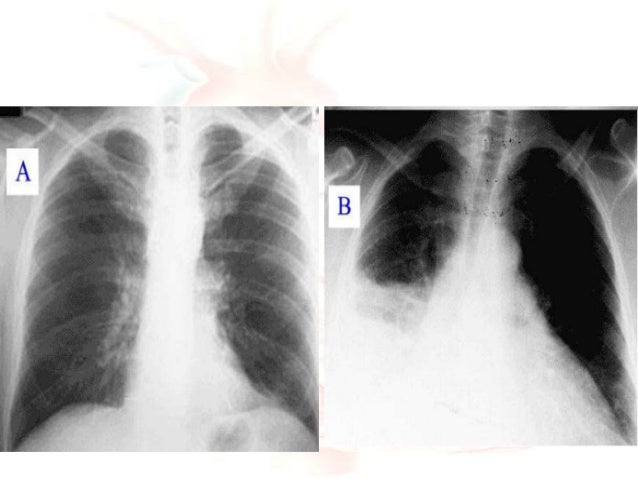

X Ray Chest Pa View Showing Lv Left Ventricular Enlargement A Large Download Scientific Diagram

A Fortified Method To Screen And Detect Left Ventricular Hypertrophy In Asymptomatic Hypertensive Adults A Korean Retrospective Cross Sectional Study